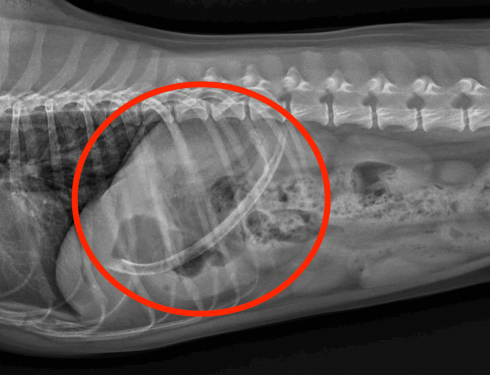

Wink arrived at the Ontario SPCA Muskoka Animal Centre underweight, in need of a bath, and with one eye almost…